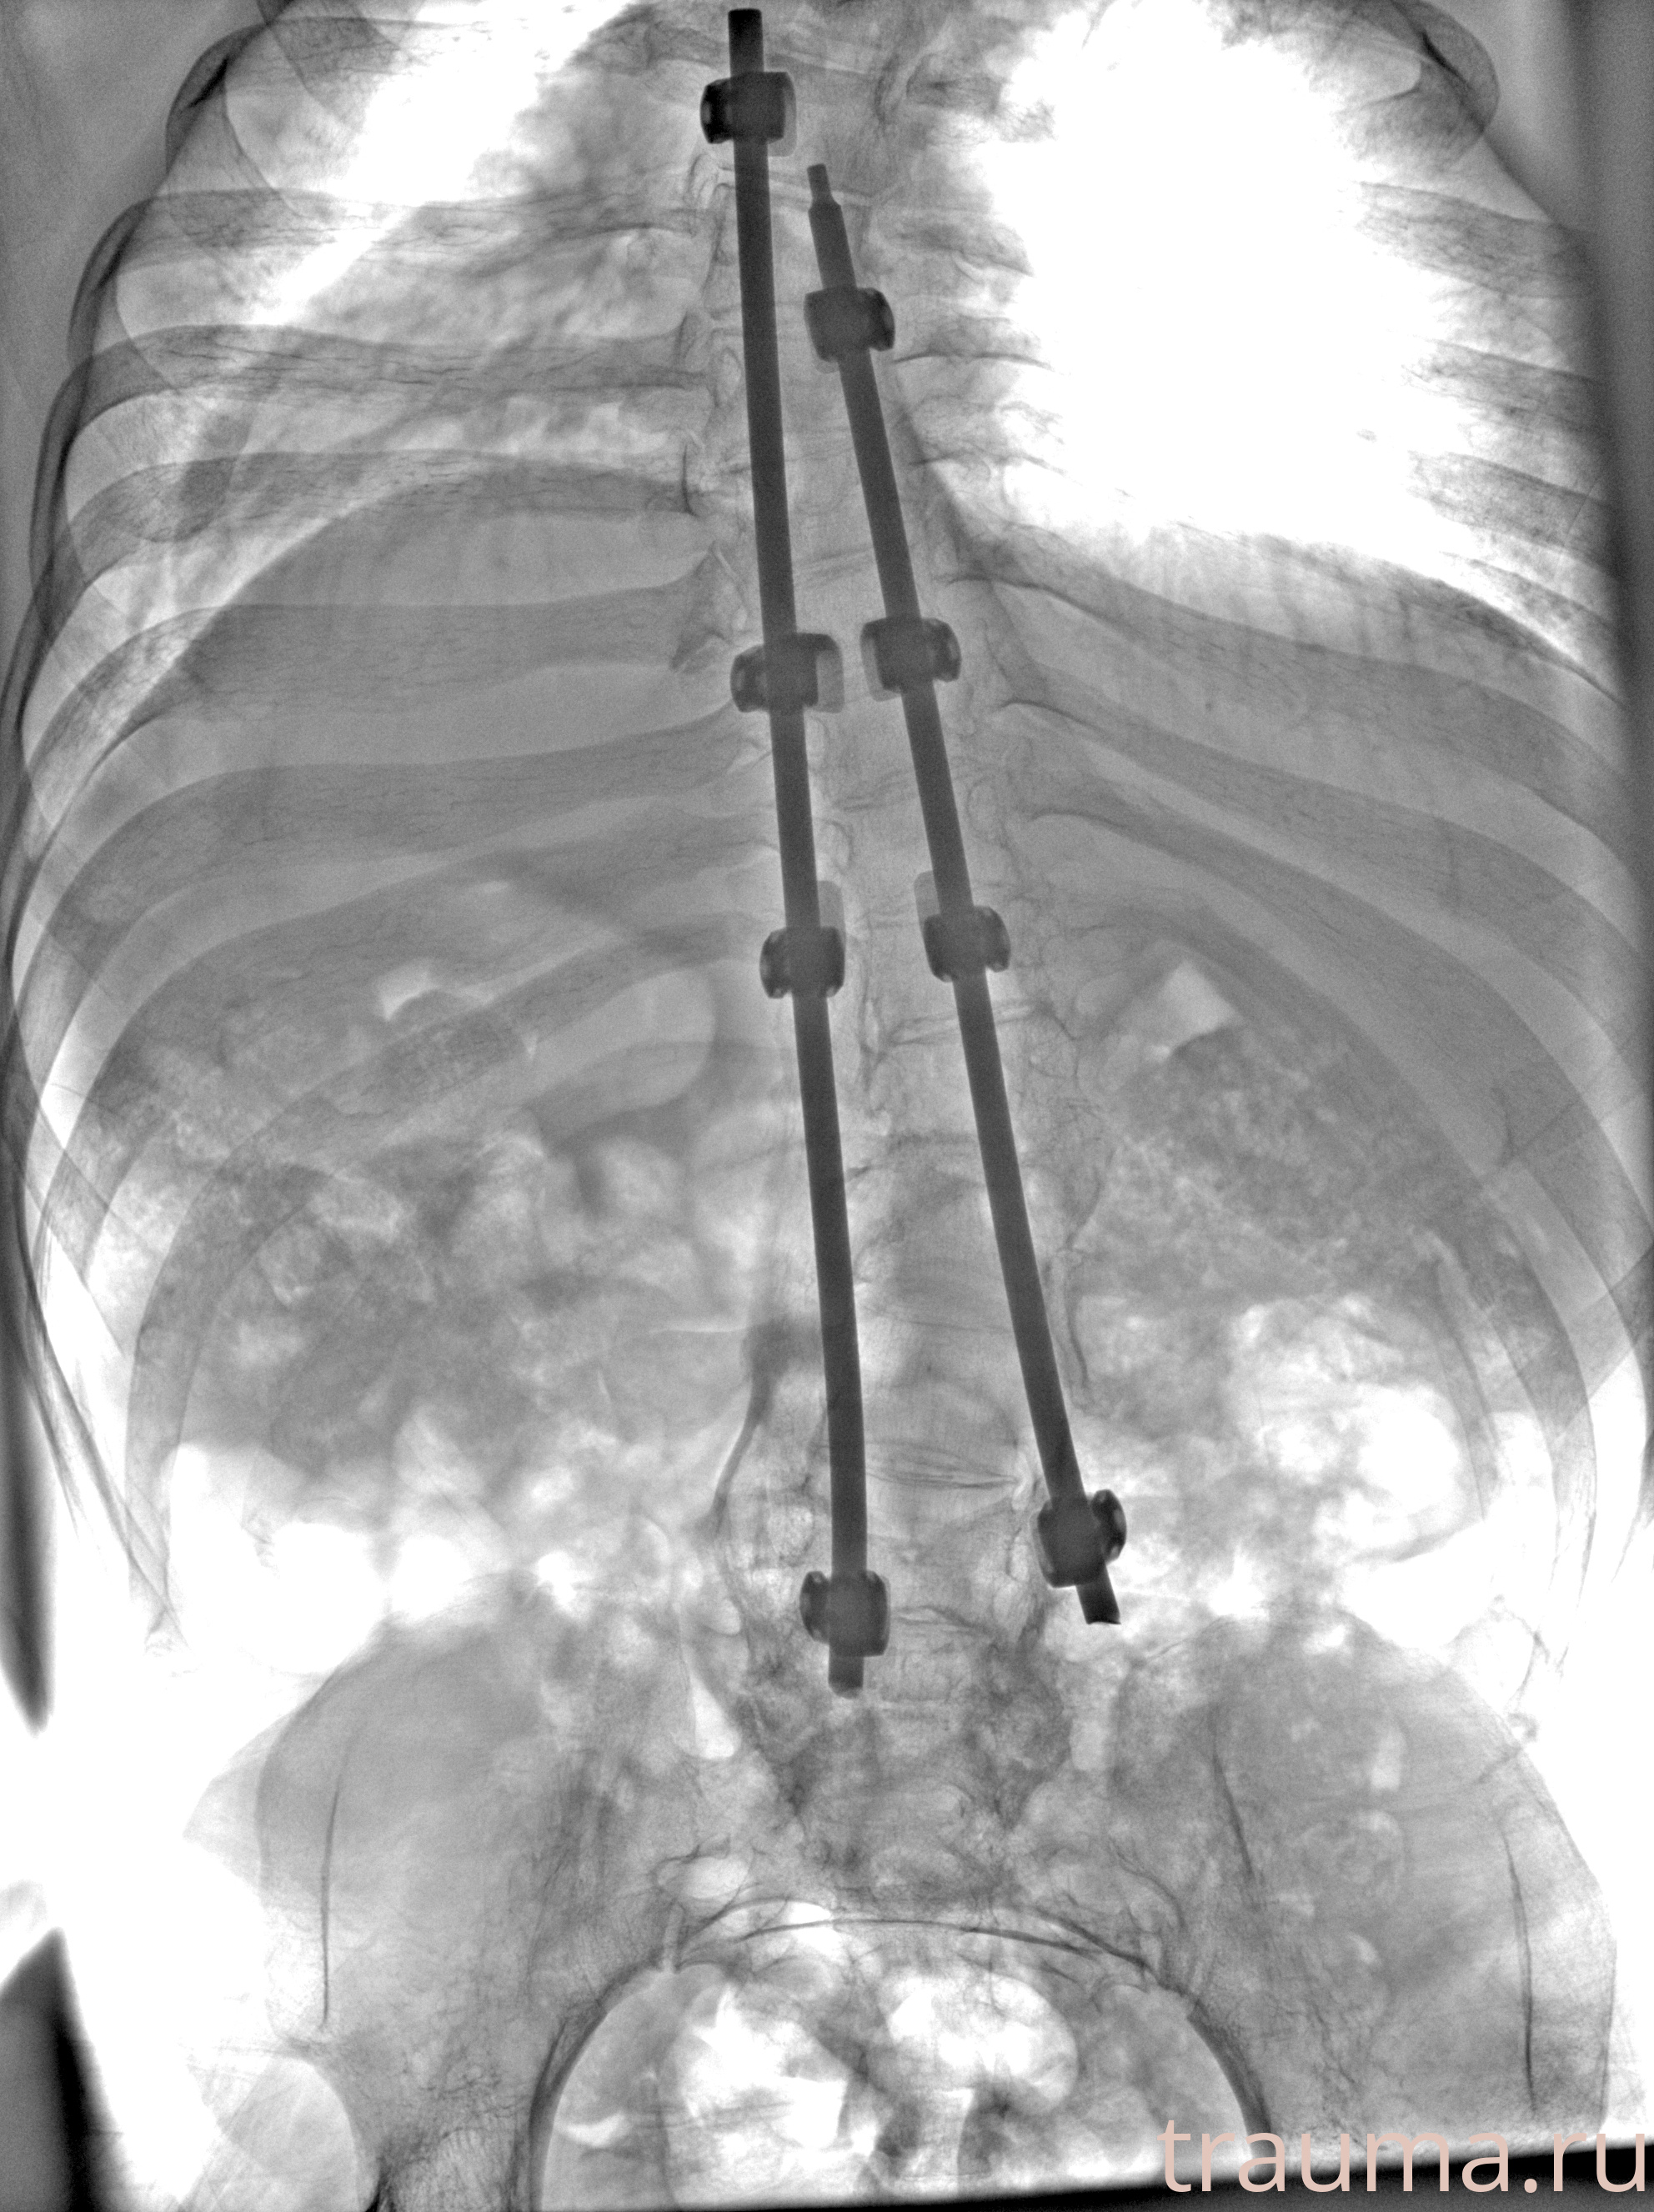

Рентгенограммы